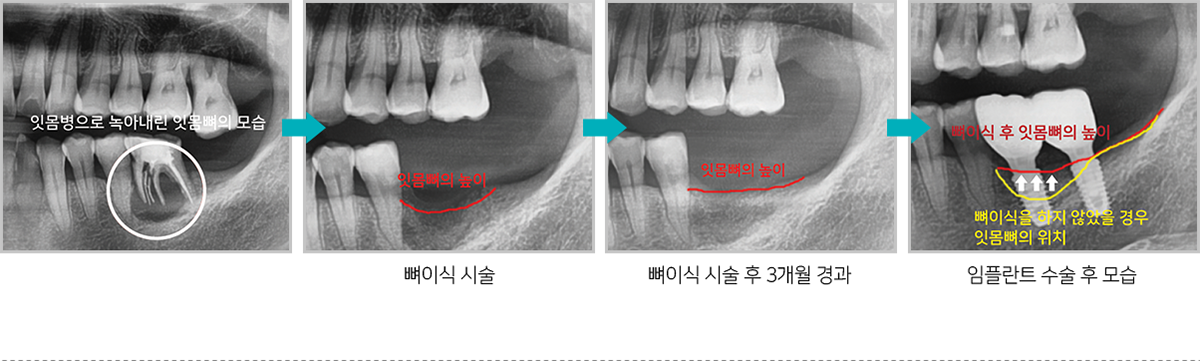

뼈이식 시술 후 잇몸뼈의 위치 변화

치조골은 치아를 발치 한 후 지속적으로 녹아

없어지는데 치조골을 보존하기 위해

발치 후

미리 뼈이식 하면 추후 임플란트 식립시 충분한

치조골을 확보할 수 있어

임플란트 수술을 하는데

매우 유리합니다.